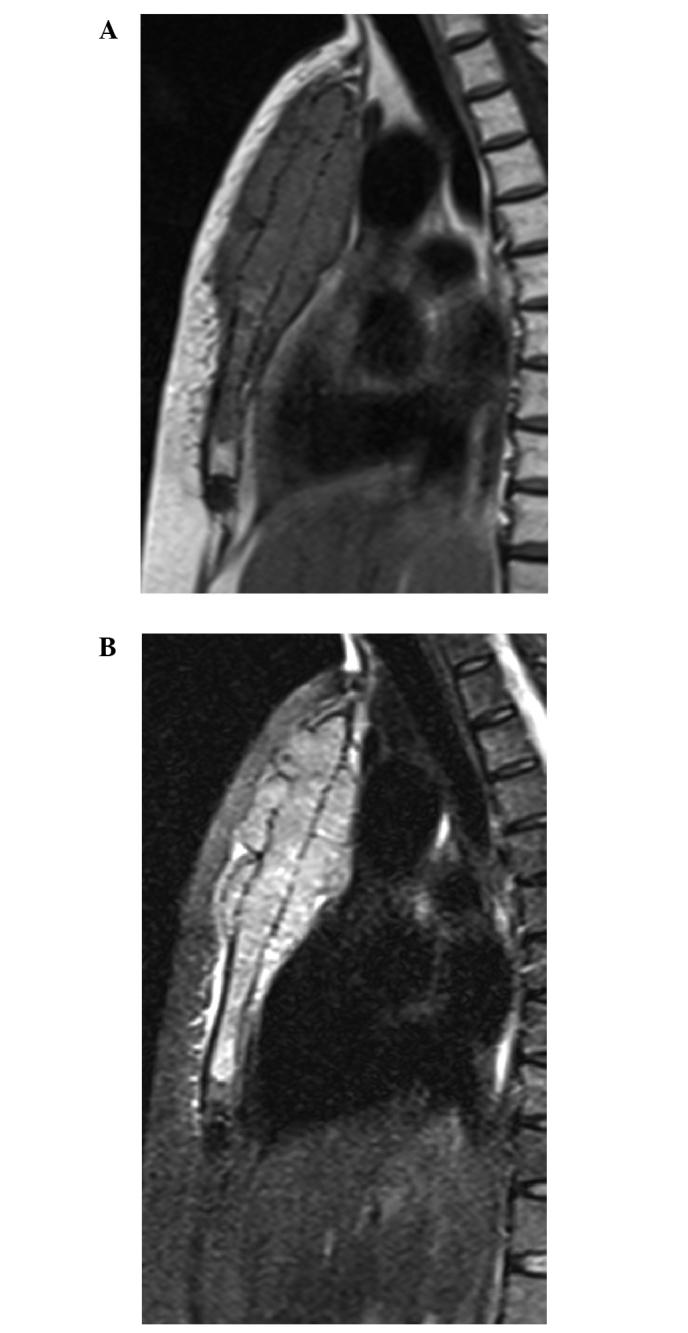

Solitary plasmacytomas (SPs) represent ≤5% of all plasma cell neoplasms and mostly occur in the spine, pelvis, ribs and pectoral girdle, while rarely occurring in the sternum. The tumors typically appear as osteolytic lesions. In rare cases, SPs can manifest as bony spicules on the surface of the bone. The present study reports the case of a 74 year-old female with an osteolytic tumor localized in the sternum. The tumor displayed extensive bony destruction, with a large quantity of thick straight spicules on the surface of the bone, resembling a sunray in appearance. The imaging, laboratory and pathological examinations of the patient met the diagnostic criteria of SP. The patient was initially treated with radiotherapy at a dose of 45 Gy. Six months later, chemotherapy consisting of vindesine, Adriamycin and dexamethasone was administered. Vindesine and Adriamycin were administered at a dose of 2 and 15 mg/day, respectively on days 1-4 in a 20-day cycle. Dexamethasone was administered at a dose of 20 mg/day on days 1-4, 9-12 and 17-20 in the 20-day cycle. In total, the patient underwent 6 cycles of chemotherapy, with a total duration of 7 months. The patient was followed-up for two years after beginning therapy. At present, the patient is well, without any evidence of progressive disease or multiple myeloma. To the best of our knowledge, this is the first case in the English literature of SP in the sternum, with an unusual sunray periosteal reaction on radiological imaging. The sites of bony spiculation in the lesions that have previously been described in the literature are the mandible, orbit, vertebral body and skull vault. To the best of our knowledge, the current study presents the first case of a SP of the sternum with a unusual spiculated periosteal reaction on radiological imaging to be reported in the English literature.